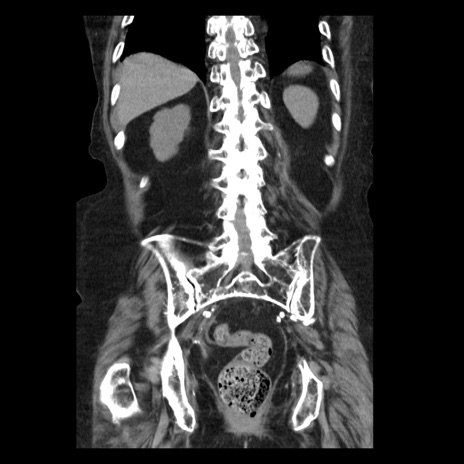

症例14(冠状断像)

【症例】 90歳代女性

【主訴】 腹痛・嘔吐

【現病歴】今朝から左側腹部痛を認めた。 経過観察していたが、嘔吐を認めたため来院。

【既往歴】 子宮癌術後

【身体所見】 意識清明、BP 127/54mmHg、P 98bpm Sp02 95%(RA)、BT 35.8°C、腹部平坦・軟腸ぜん動音聴取良好、右下腹部圧痛(+) 反跳痛なし

【データ】WBC 9800、CRP 0.46